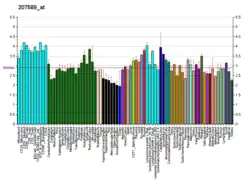

- Gonzalez-Cabrera PJ, Gaivin RJ, Yun J, et al. (2003). "Genetic profiling of alpha 1-adrenergic receptor subtypes by oligonucleotide microarrays: coupling to interleukin-6 secretion but differences in STAT3 phosphorylation and gp-130". Mol. Pharmacol. 63 (5): 1104–16. doi:10.1124/mol.63.5.1104. PMID 12695539. S2CID 10868191.